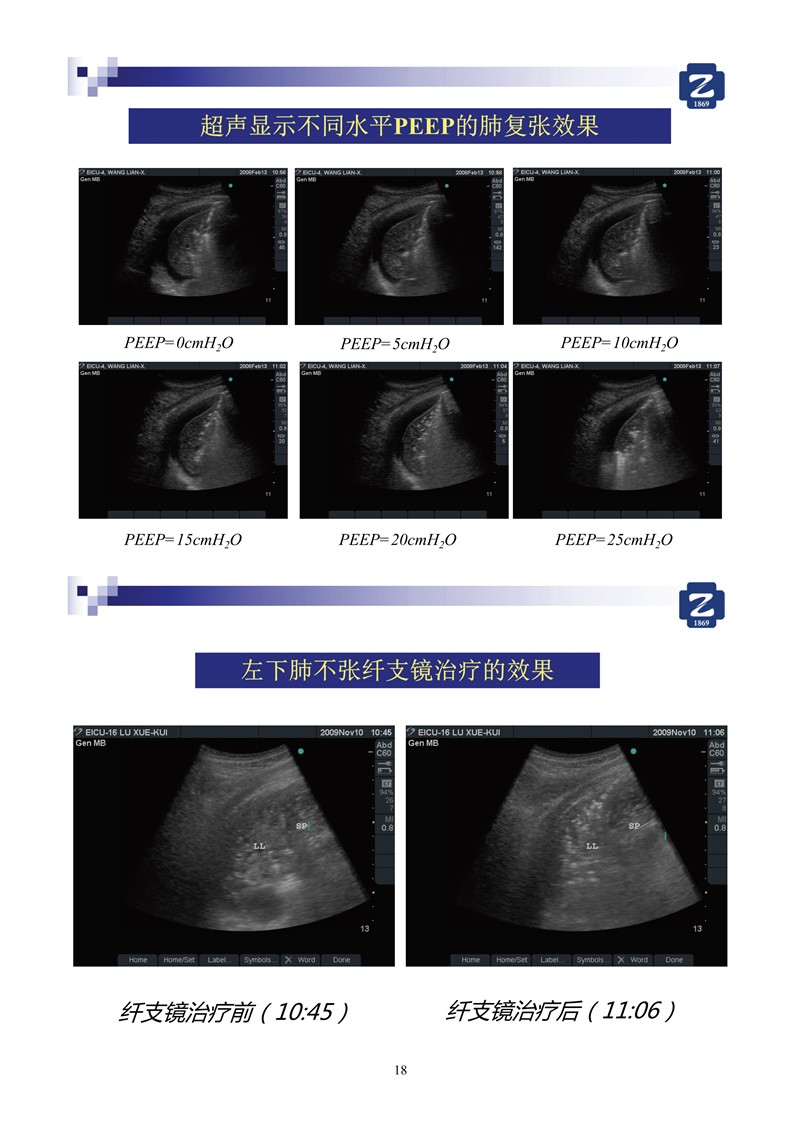

第一版新型冠狀病毒肺炎超聲診斷實(shí)用手冊(全文)

新冠肺超聲實(shí)用手冊(2)_35.jpg